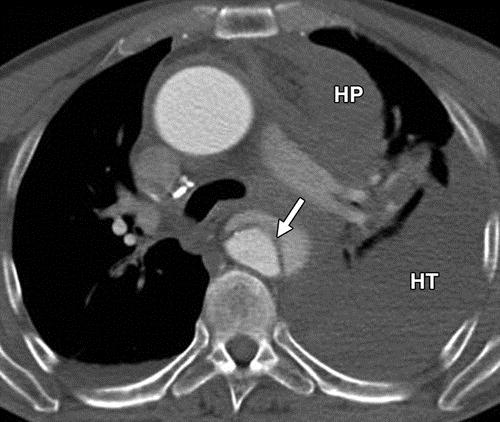

胸、背、腹痛,怀疑夹层?CT平扫,细微之处见功